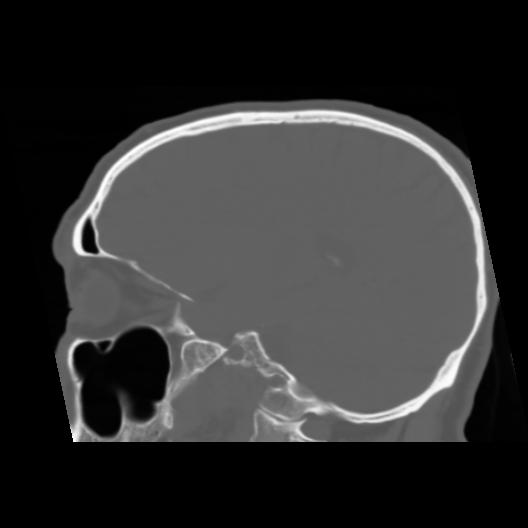

6 CEREBRO,,Sagittal,3.000,CEREBRO,Sagittal,